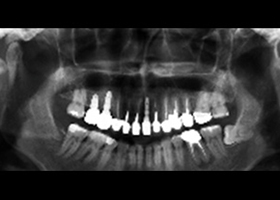

治療前,全口X光片。